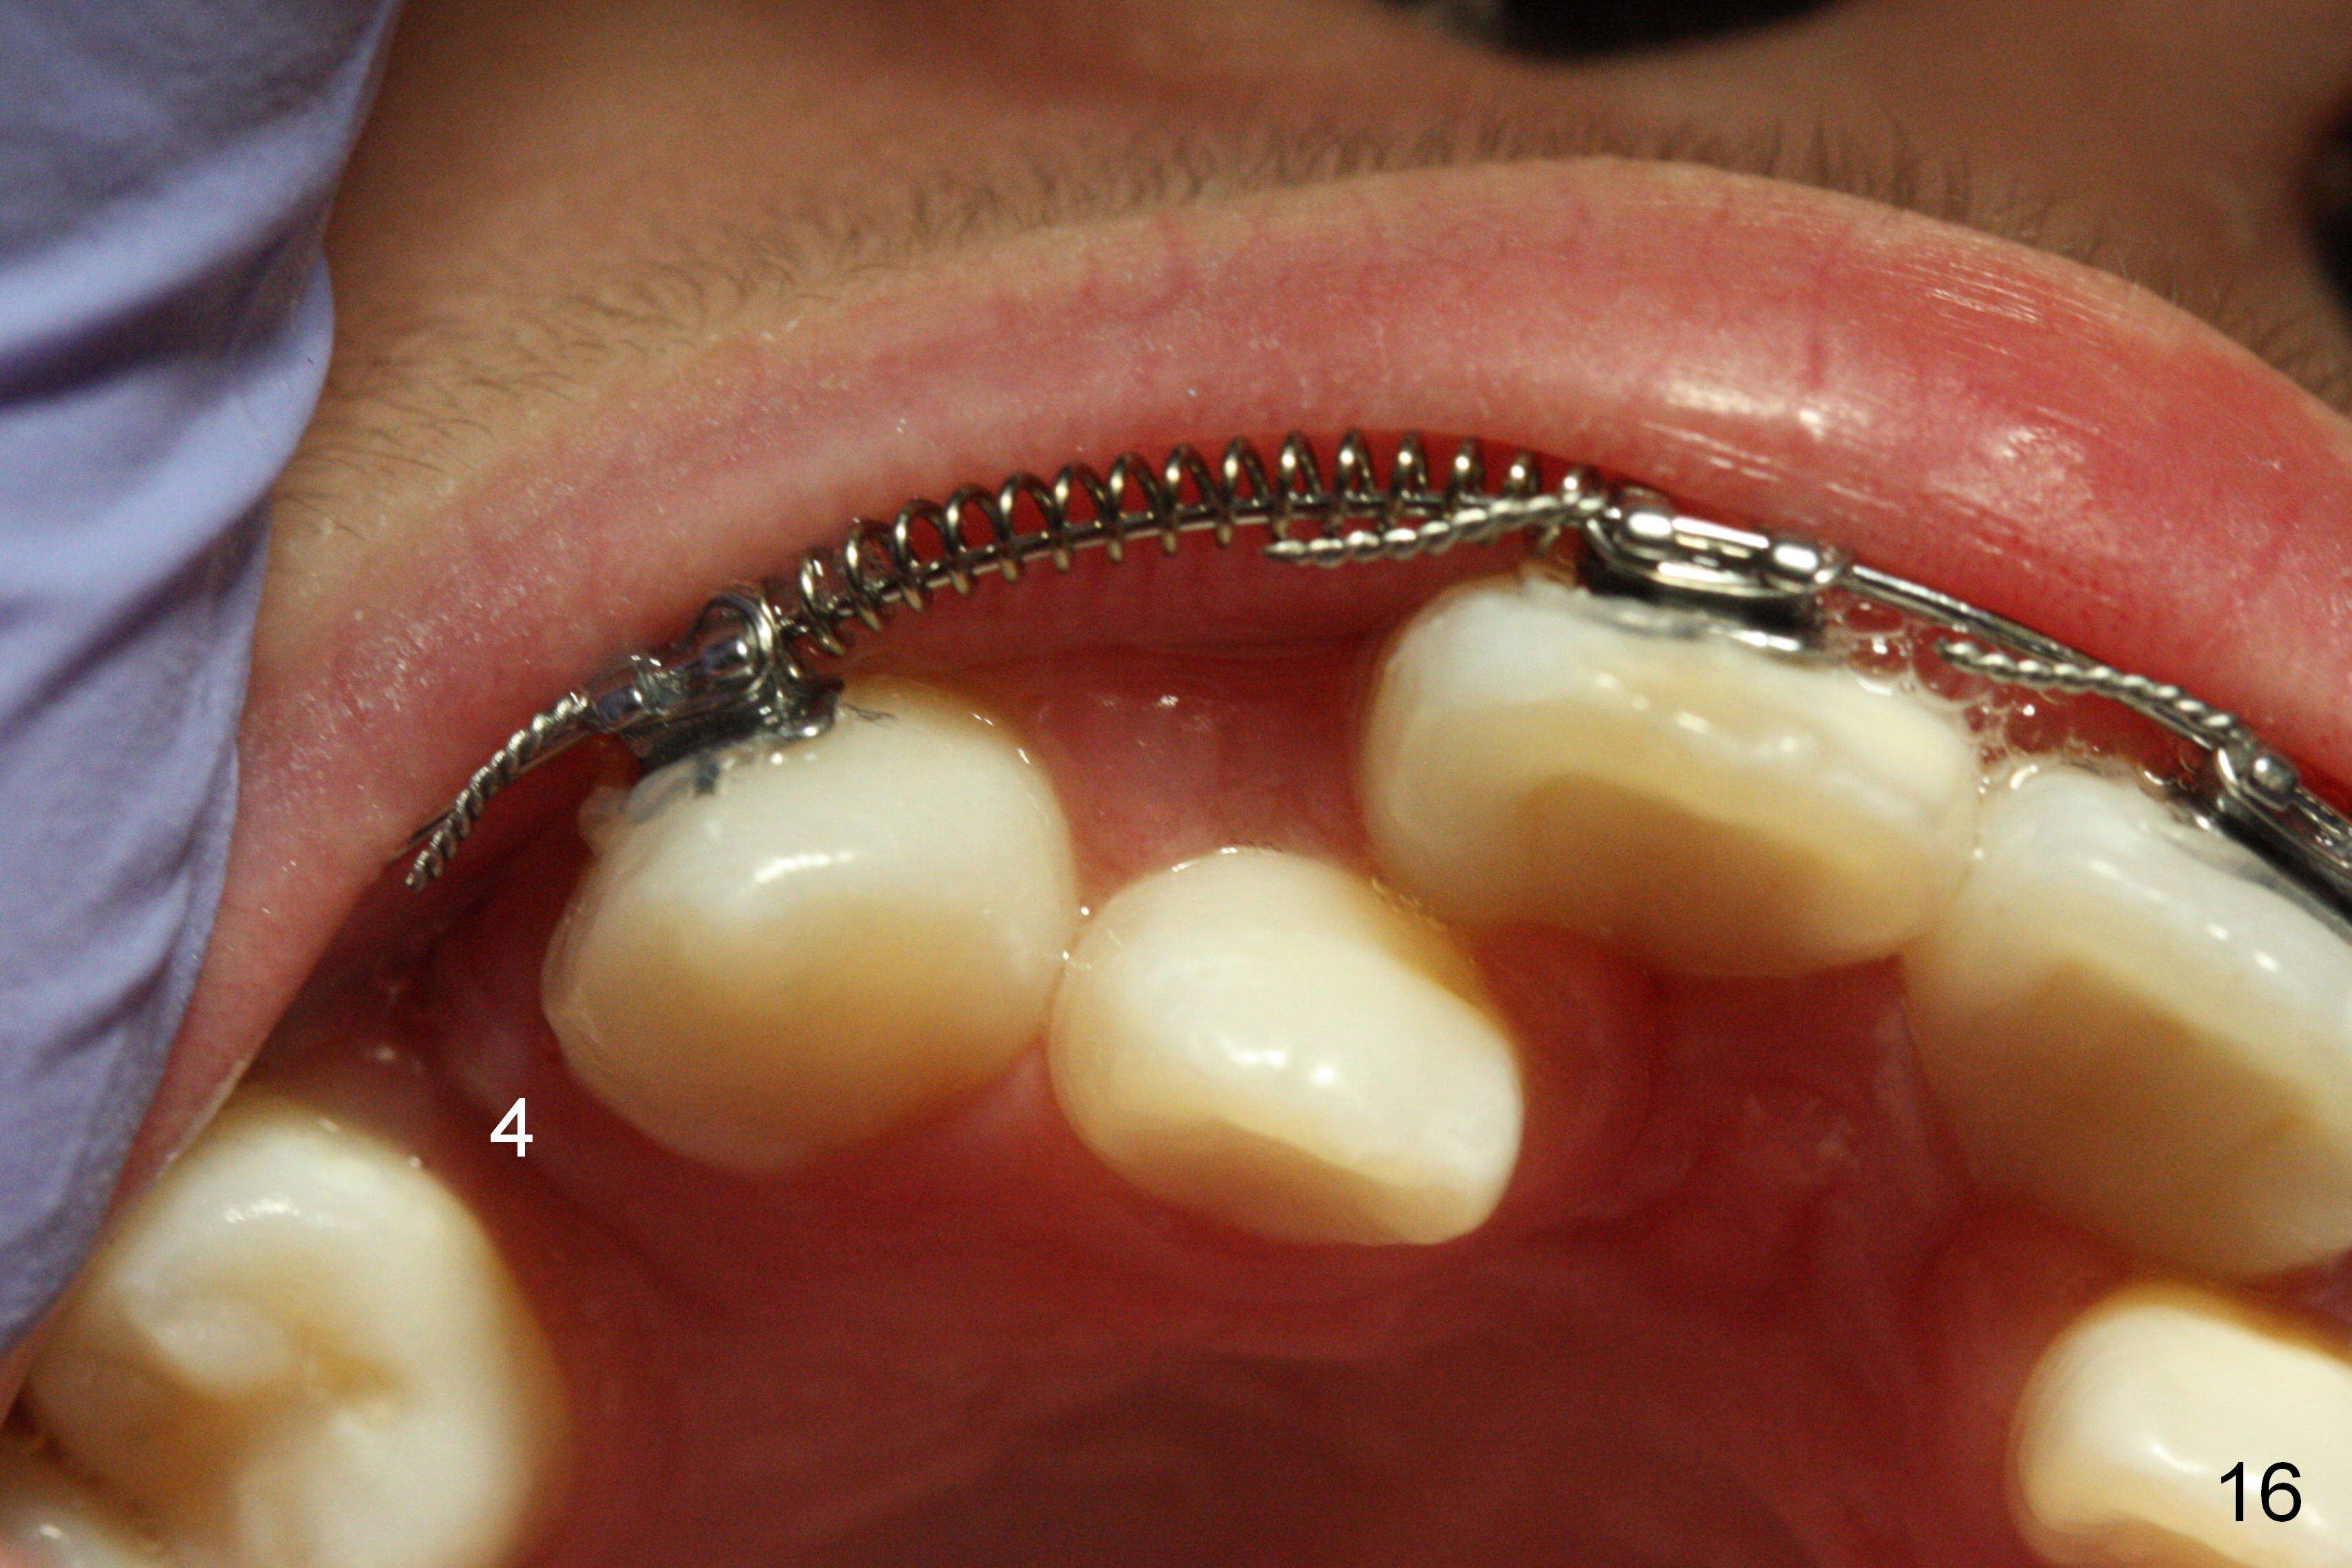

Another 1 month, the right canines (Fig.14: 3, as compared to the left side (Fig.15)) occlude each other, while LR2 has full engagement into .016 niti wire (compare to Fig.12,13). Open coil springs are placed with upper .018' ss arch wire. It must be easier to gain space for UR 2 (Fig.16) than UL2 (Fig.17), because of the presence of space on the right side (4 in Fig.16). There appears no space between UL 4 and 6.

Three visits after open coil spring and 1 visit after sling shot, U2 cross bite is corrected (Fig.18,19). Due to UR2 rotation (Fig.19), bracket cannot be placed (Fig.20, 16 niti). Power chain x 3 is placed between UR2 and 3 to gain space for bracketing, which turns out not working. UL2 bracket is placed upside down for torque.